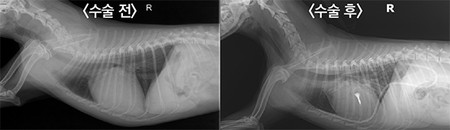

의료진은 최소 절개 늑간 개흉술을 통해 심장에 직접 접근, 경식도 초음파 가이드 하에 14mm 크기의 V-clamp device를 이첨판막에 장착하는 수술을 시행했다. 그 결과 수술 직후 환견의 이첨판 역류증 혈류가 수술 전보다 확연하게 감소했으며, 빠른 회복 추세를 보여 더 이상 이뇨제는 투여하지 않는다.